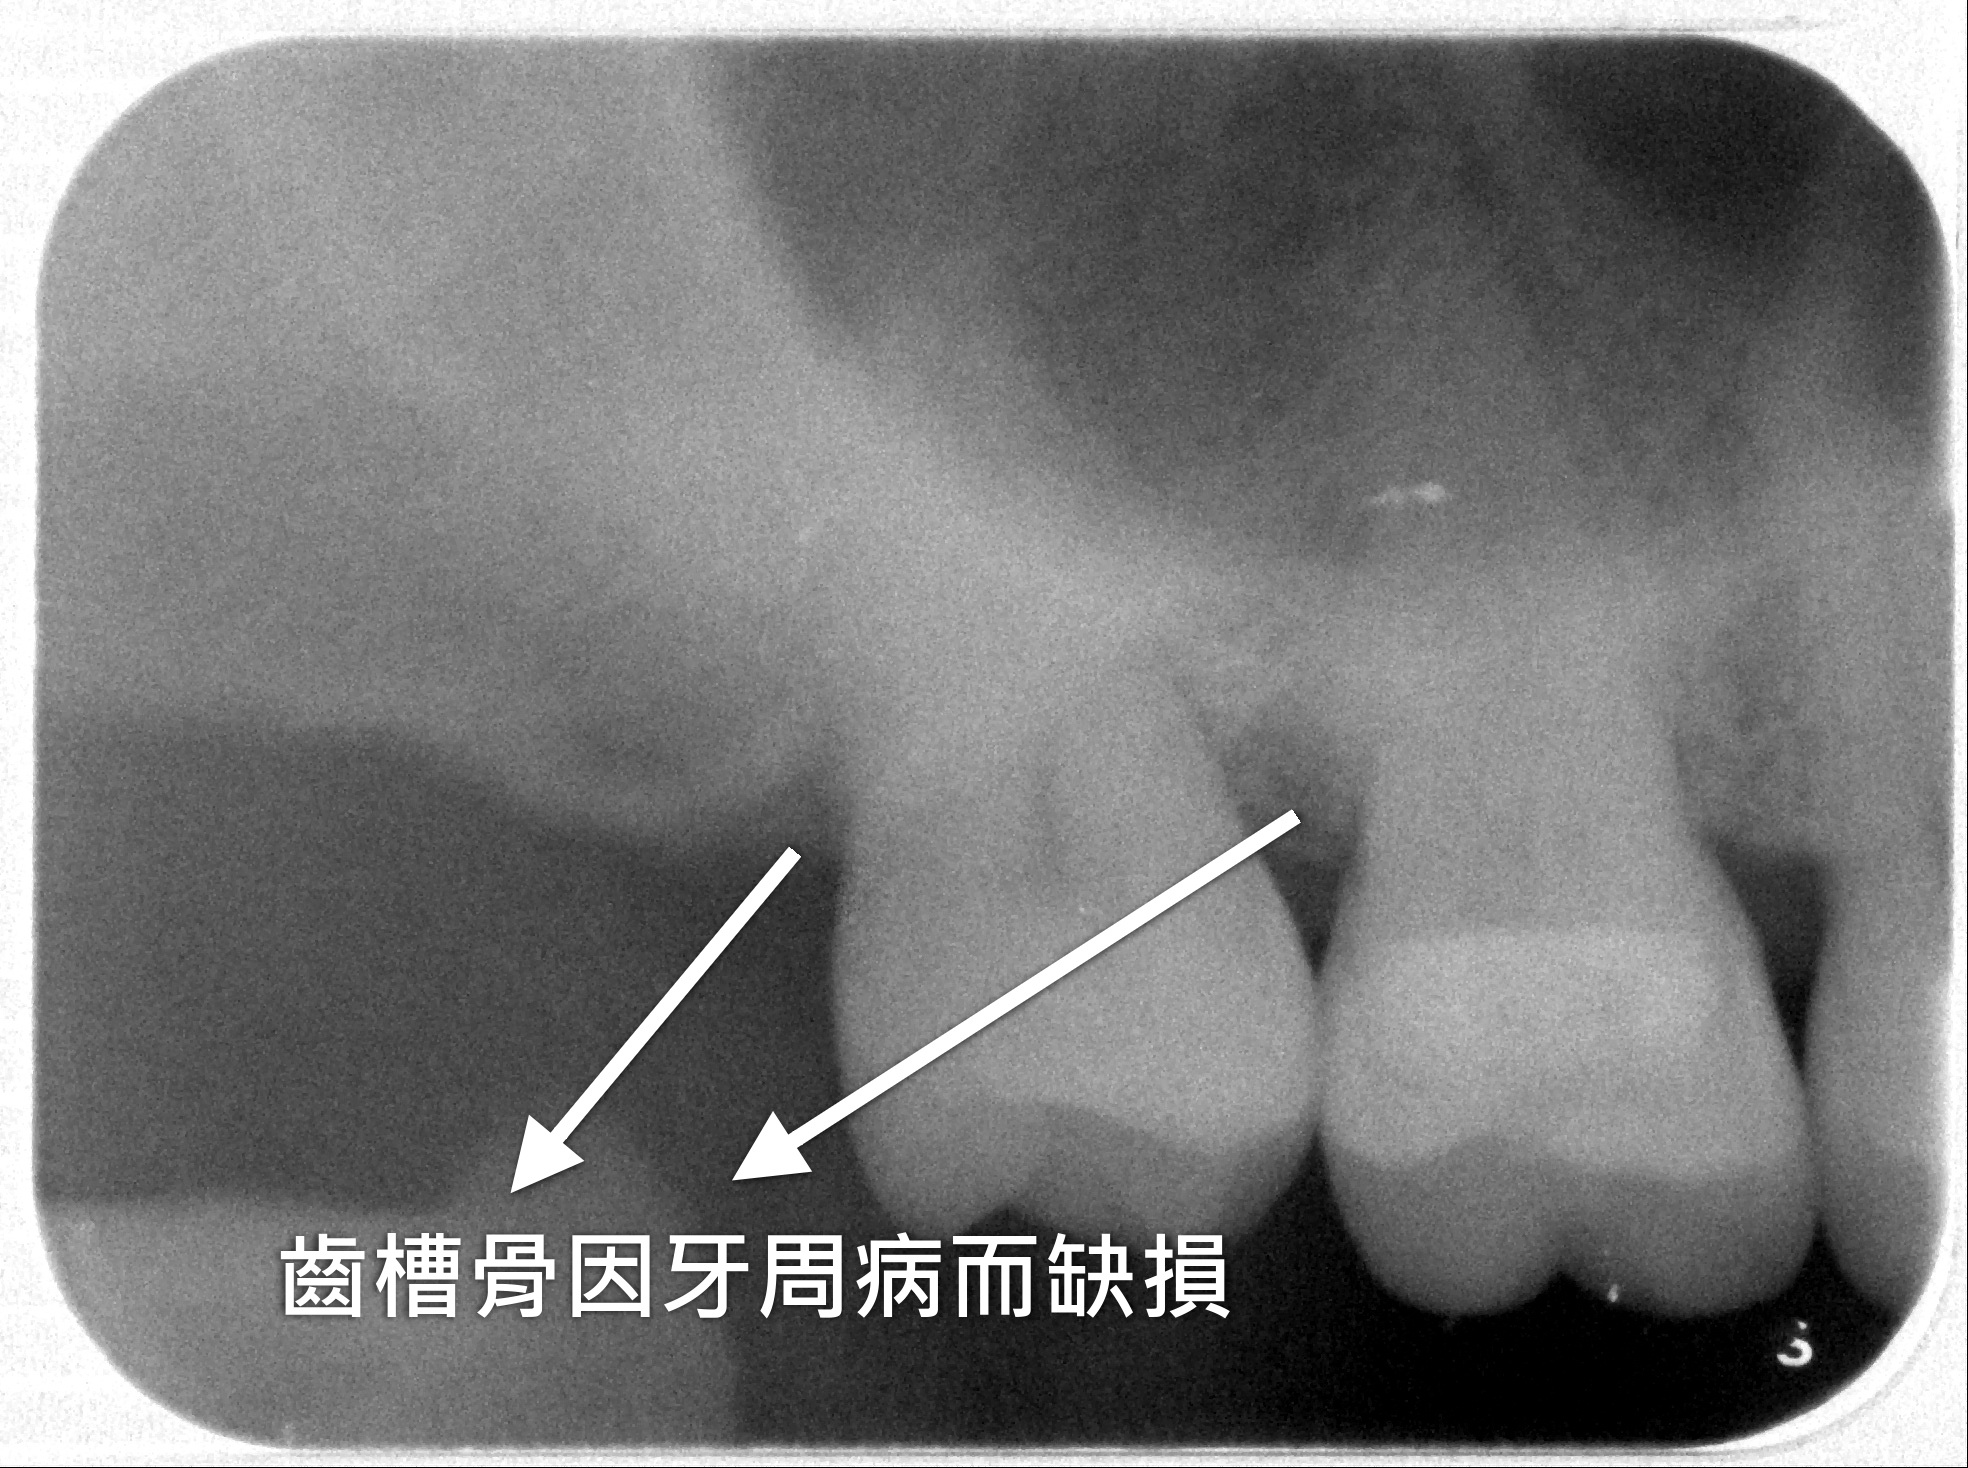

臺北榮民總醫院桃園分院牙科主任王碩說明:除平時居家的口腔照護外,牙周病患者應接受牙周階段性的治療,包含治療前的臨床評估、洗牙及口腔清潔衛教,以及牙齦下結石清除與牙根整平治療、移除不合的假牙與牙齒填補材料、拔除因牙周破壞過重或其它不可逆原因而無救的牙齒,與牙周治療後的重建。對於牙周病較為嚴重但仍可保留的牙齒,須再視病況接受牙周手術治療,透過手術治療,能針對一般非手術療程無法處理的牙周深處進行清創,也能改善牙齦深溝、牙齦型態異常等問題,或者對於牙齦萎縮處進行軟組織修復。若牙齒周圍因牙周病而導致齒槽骨缺損,還須接受骨修整或補骨手術,透過移除過於隆凸且不當的齒槽骨表面,以及利用骨粉等材料,讓骨缺損處得以再生骨組織,達到齒槽骨形態的調整與重塑,恢復平整穩定的齒槽骨環境,進而獲得良好的牙周狀態。